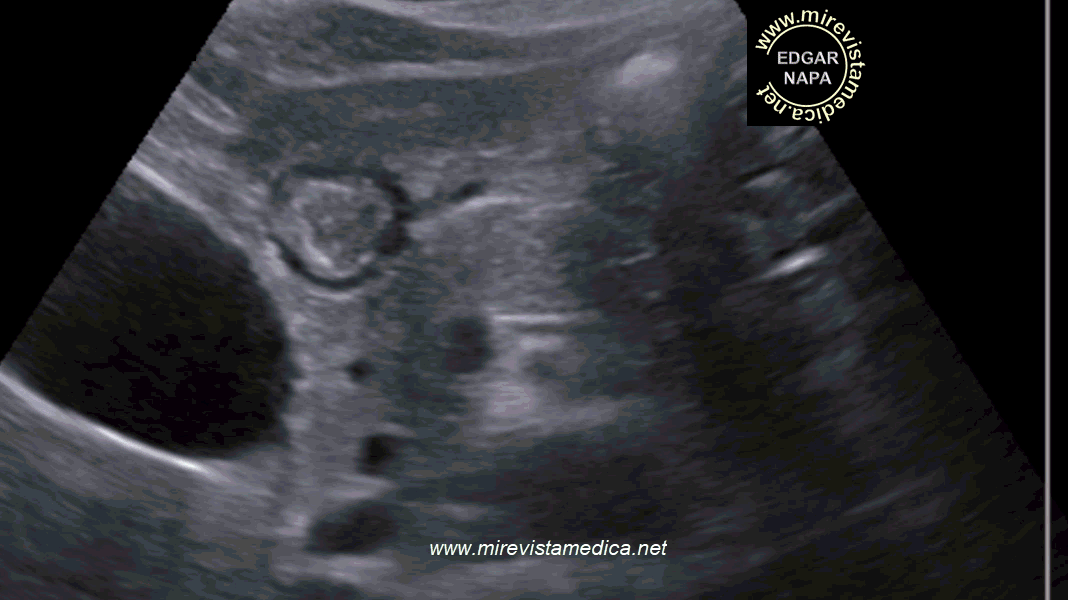

ULTRASONIDO (US_)